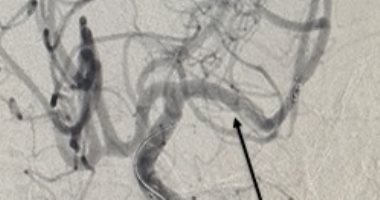

وأضاف الدكتور فيصل جودة، مدير عام مستشفى شبين الكوم التعليمي، فور وصول المريض إلى مستشفى شبين الكوم التعليمي، استعد فريق المخ والأعصاب بالطوارئ لاستقباله وتقييمه، وتبين أن المريض يعاني من اشتباه جلطة بالقلب بالتزامن مع أعراض الجلطة المخية، وهو ما استدعى تدخلاً مشتركًا وغير مسبوق بين فريقي القسطرة القلبية والمخية، وتم تجهيز المريض لإجراء قسطرة تشخيصية على القلب بالتزامن مع إجراءات القسطرة المخية، وبينما أظهرت القسطرة القلبية سلامة شرايين القلب، كشفت القسطرة المخية عن وجود انسداد بالشريان الأوسط للمخ بالناحية اليسرى. وعلى الفور تم التعامل معها وسحبها بنجاح، وخرج المريض إلى وحدة السكتة الدماغية للمتابعة وتلقى العلاج بعد استقرار حالته.

وأفاد الدكتور أحمد محمد عطية استشاري المخ والأعصاب والقسطرة المخية بالهيئة بأن وحدات القسطرة المخية بمستشفيات الهيئة تعمل كمنظومة واحدة فى إطار من لاتعاون والتكامل فيما بينها، مما يسهم فى الحفاظ على حياة المرضى وعدم تعرضهم لأية مضاعفات نتيجة التأخر فى التدخل فى الوقت المناسب، والتعامل مع هذه الحالة يؤكد ذلك، حيث تم استقبالها بمستشفى دمنهور التعليمي والتعامل فوراً معها والتنسيق مع مستشفى شبين الكوم التعليمي للتجهيز لاستقبال الحالة، وتمكن الفريق الطبى من التخل فى الوقت المناسب وانقاذ المريض، وساهم في هذا الإنجاز الطبي الهام فريق القسطرة المخية والقلبية بمستشفى شبين الكوم التعليمي الدكتورأحمد شاهين استشاري القلب، الدكتور أحمد محمد عطية ..استشاري المخ والأعصاب والمشرف على وحدة القسطرة المخية، د. أحمد هاني الشافعي .. زميل مساعد الأمراض العصبية، د. شعبان أحمد معوض زمالة الأمراض العصبية، ومحمد سامي تمريض القسطرة، وأحمد خضر فني القسطرة، وذلك تحت إشراف رئيس قسم المخ والأعصاب والطب النفسي بشبين الكوم التعليمي والدكتورة رباب نشأت أبوشادي، وبالتعاون مع أطباء طوارئ الأمراض العصبية والسكتة الدماغية بمستشفى شبين الكوم التعليمي د. ياسمين أحمد، د. روان الشيخ، ود. إيمان الزوق، وأطباء القسطرة القلبية بشبين الكوم التعليمي: وعلى رأسهم الدكتور إيهاب المليجي، رئيس قسم القلب ووحدة القسطرة، لجهودهم السريعة وتعاونهم المثمر، إضافة إلى الجهد المشكور لسرعة التنسيق ونقل الحالة من الدكتور ابراهيم البنا مدير مستشفى دمنهور التعليمي، والدكتور محمد البهنساوي رئيس قسم الأعصاب.